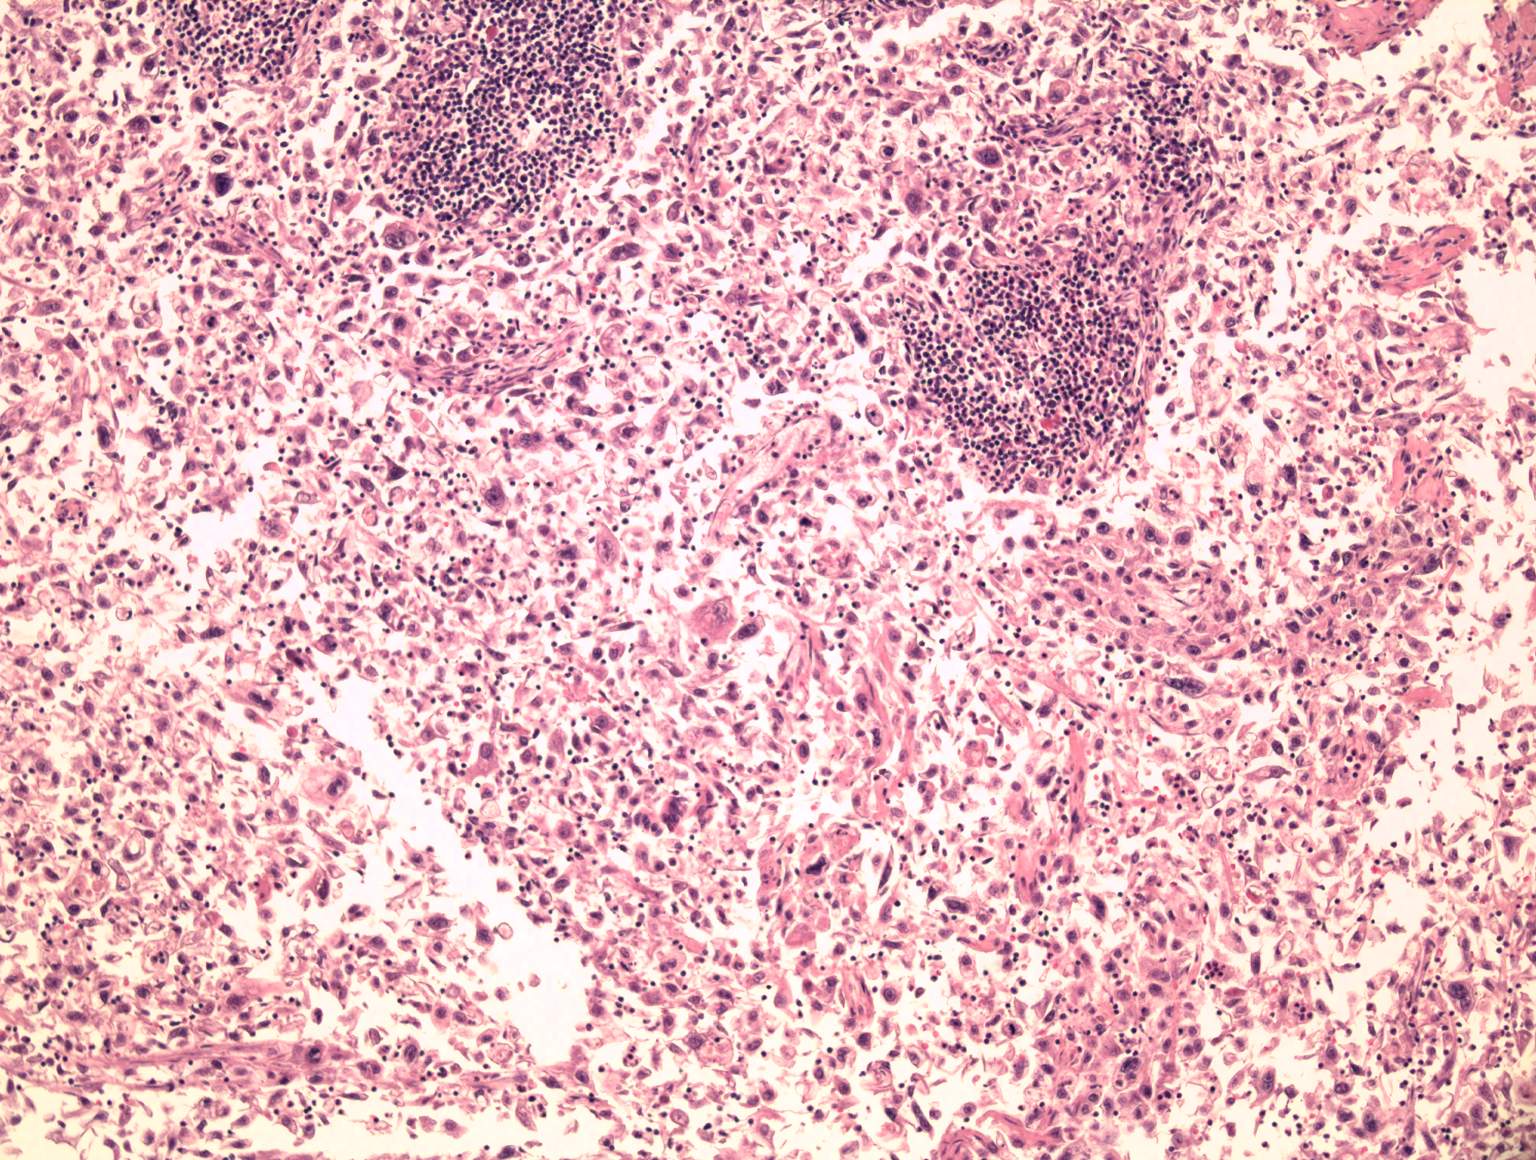

Undifferentiated carcinoma with ductal and

adenosquamous component

detail: x40

Adenosquamous component with keratinization

Note: pathological, tripolar mitosis |